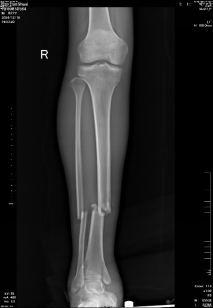

患者,男,22岁,车祸致右小腿疼痛肿胀,经X片检查提示:右胫腓骨折骨折。